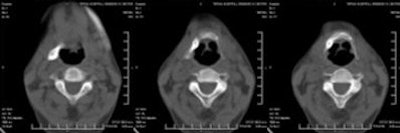

CT scan showed the presence of ossification of the right stylohyoid chain articulating with the hyoid bone. An elongated styloid process was present on the left side.